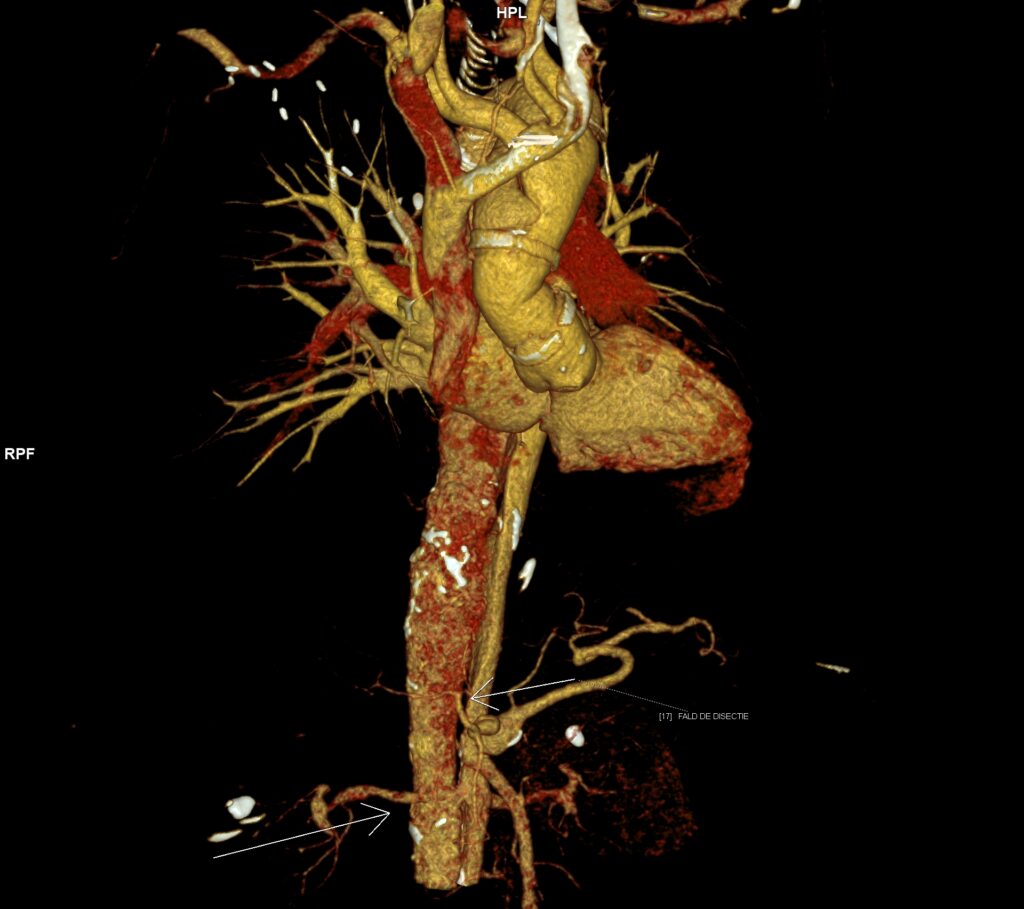

Figura 3: reconstrucție VRT din angioCT arterial

Discuţie caz nr 126: Investigația CT a fost realizată pentru control postoperator la un pacient cu proteză de aorta ascendentă pentru disecție de aorta Stanford tip A operată. Se evidențiază proteză de aortă ascendentă în poziție normală, fără dezvoltări anevrismale la nivelul anastomozelor precum și disecție de aorta toracică și abdominală restantă cu orificii de intrare proximal precum și distal în vecinătatea originii arterei renale drepte, iar faldul de disecție nu evoluează la nivelul ramurilor. În plus, se evidențiază stenoză proximală de trunchi celiac cu dilatație poststenotică